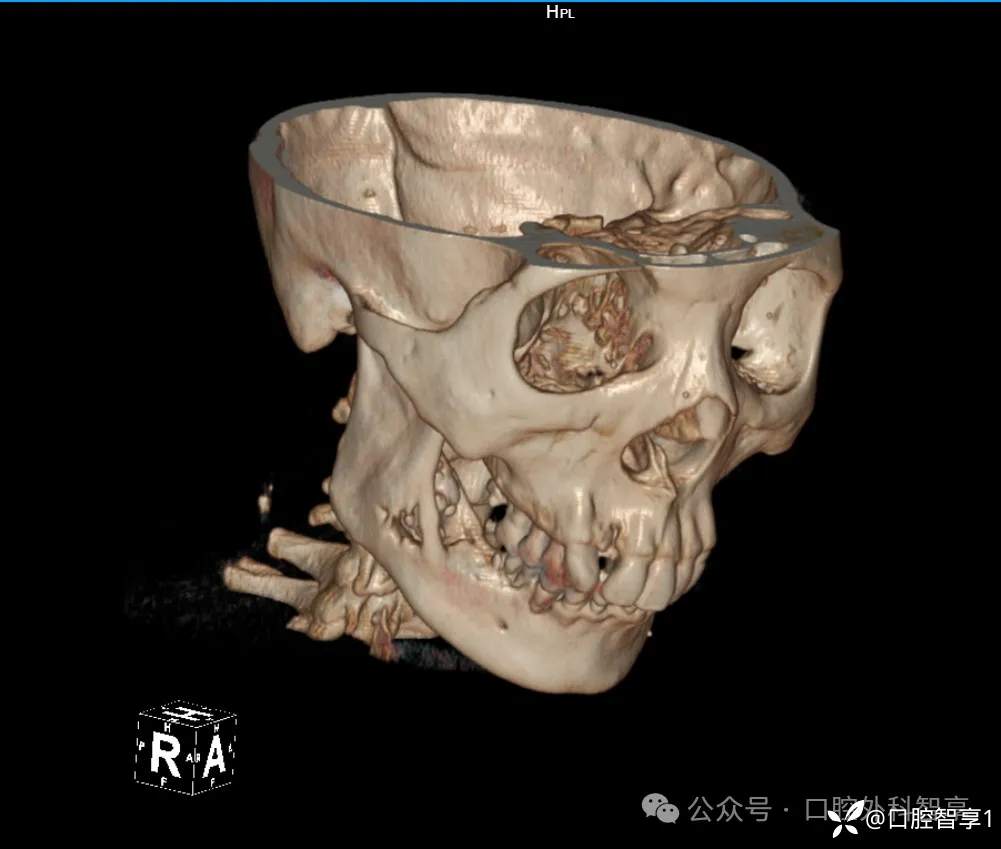

下颌骨CT示:右下颌角密度不均匀,病变部位累及下牙槽神经管,内可见下颌第三磨牙。

【临床诊断】:颌骨骨髓炎、阻生牙